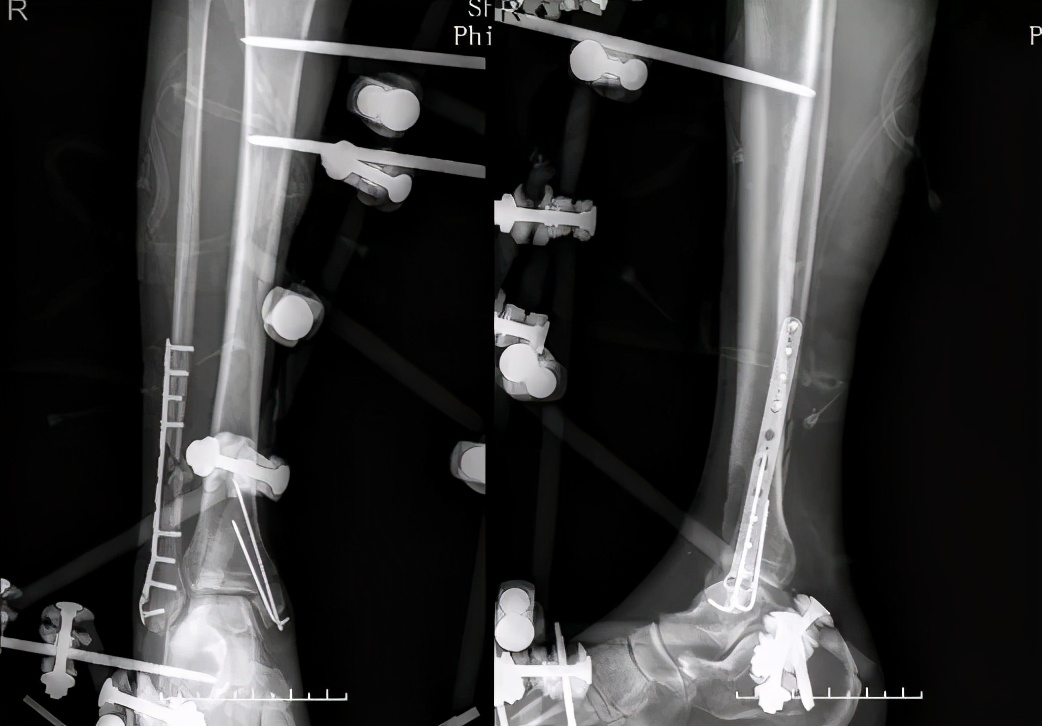

(术后右胫腓骨正侧位)

术中按照右小腿皮肤缺损形状于双大腿前侧画出相应大小皮瓣,其中左大腿前外侧画出30*10cm大小的皮瓣,先于一侧切开皮肤找到穿支动脉后游离皮瓣,清除皮下脂肪组织,将切取的皮瓣于右小腿和踝部皮肤缺损处覆盖,吻合动脉,置负压引流术,修整后缝合皮瓣,术中测试见皮肤血供良好,供区创面直接缝合。